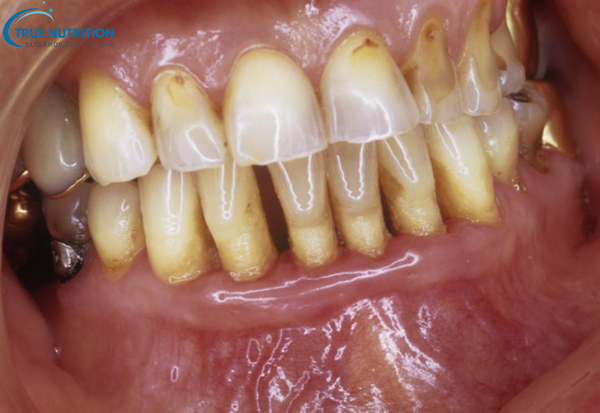

Triệu chứng viêm nha chu

Viêm nha chu thường có những triệu chứng rõ rệt, giúp nhận biết bệnh ngay từ giai đoạn đầu. Các triệu chứng bao gồm:

- Nướu bị sưng và đỏ: Nướu trở nên mềm, sưng, có màu đỏ tươi hoặc đỏ sẫm.

- Nướu dễ chảy máu: Nướu sẽ chảy máu khi đánh răng hoặc dùng chỉ nha khoa.

- Răng lung lay: Khi các mô xung quanh răng bị tổn thương, răng có thể bị lung lay hoặc di chuyển.

- Hôi miệng: Vi khuẩn trong mảng bám có thể gây hôi miệng kéo dài.

- Mủ giữa răng và nướu: Viêm nha chu nặng có thể khiến xuất hiện mủ giữa nướu và chân răng.

- Khoảng trống giữa răng và nướu: Viêm nha chu gây ra các túi nha chu, làm cho răng có khoảng trống, khiến chúng có vẻ dài hơn bình thường.